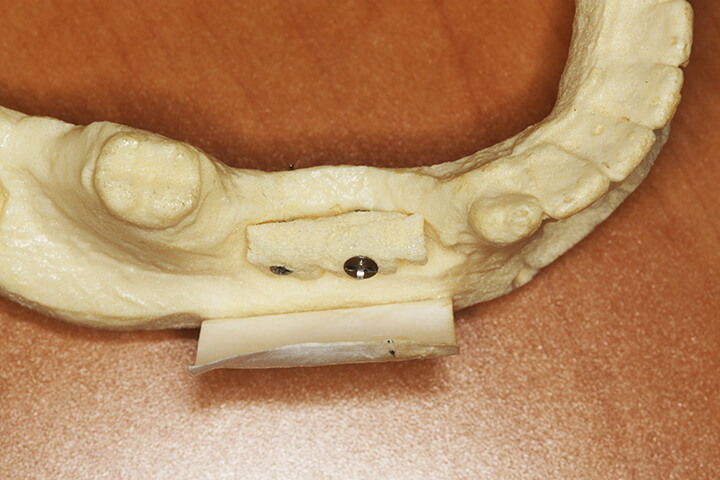

Ridge Grafting:

Ridge grafting is reserved for situations where there has been marked bone loss at the site planned for implant placement. In these cases, the patient’s own bone is harvested from an adjoining area and fixated at the planned implant site. Cadaver bone and membrane material are also added to enhance healing. Implant placement is performed after bone maturation is complete.